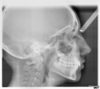

Les radios après le traitement